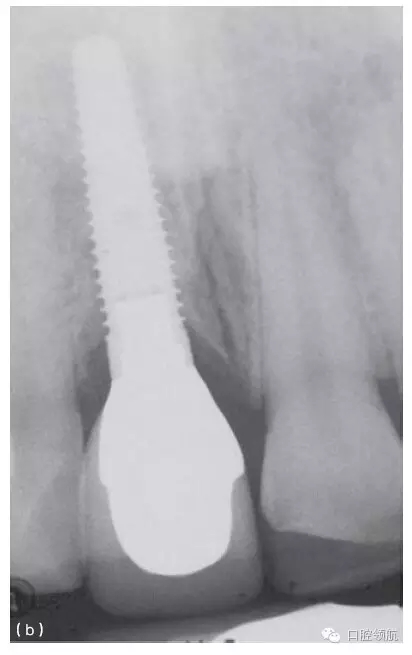

其他的美學問題與種植體植入位置不當(圖10.20a,b),以及植入前存在骨吸收有關。骨吸收的存在使種植體無法植入到理想位置,造成單冠之間或是固定局部義齒的橋體之間存在頸部間隙(圖10.21)。

圖10.20 (a)中切牙種植體的位置太偏唇側,采用定制的基臺盡可能補償頰側的錯位。(b)一并更換相鄰的兩個冠修復體以獲得更滿意的結果。

種植體適當?shù)那蓄i/ 頸向位置,有利于建立逐漸過渡的外形和正常的穿齦形態(tài)。種植體切頸/牙合頸向的定位,很大程度上取決于現(xiàn)存骨的位置(圖10.33a~c),以及滿足美學需求的頸部過渡形態(tài)。因為種植體的平臺接口為小直徑的圓形,而齦緣的修復體截面為直徑較大的不規(guī)則幾何形態(tài),中間需要一定的過渡才能滿足美學的需求。一般來說,種植體植入到鄰牙釉牙骨質界稍下方,以使所需的形態(tài)學改變逐步發(fā)生(圖10.34)。

圖10.33 (a)金屬烤瓷冠粘結后的根尖片。(b)種植體位于鄰牙釉牙骨質界根方3mm的根尖片。切嵴到種植體頂部的距離太大,導致種植體金屬部件可能承受較大的力。(c)種植體植入到嚴重骨吸收的上頜第一前磨牙區(qū)。種植體到面的距離幾乎等于種植體的長度。